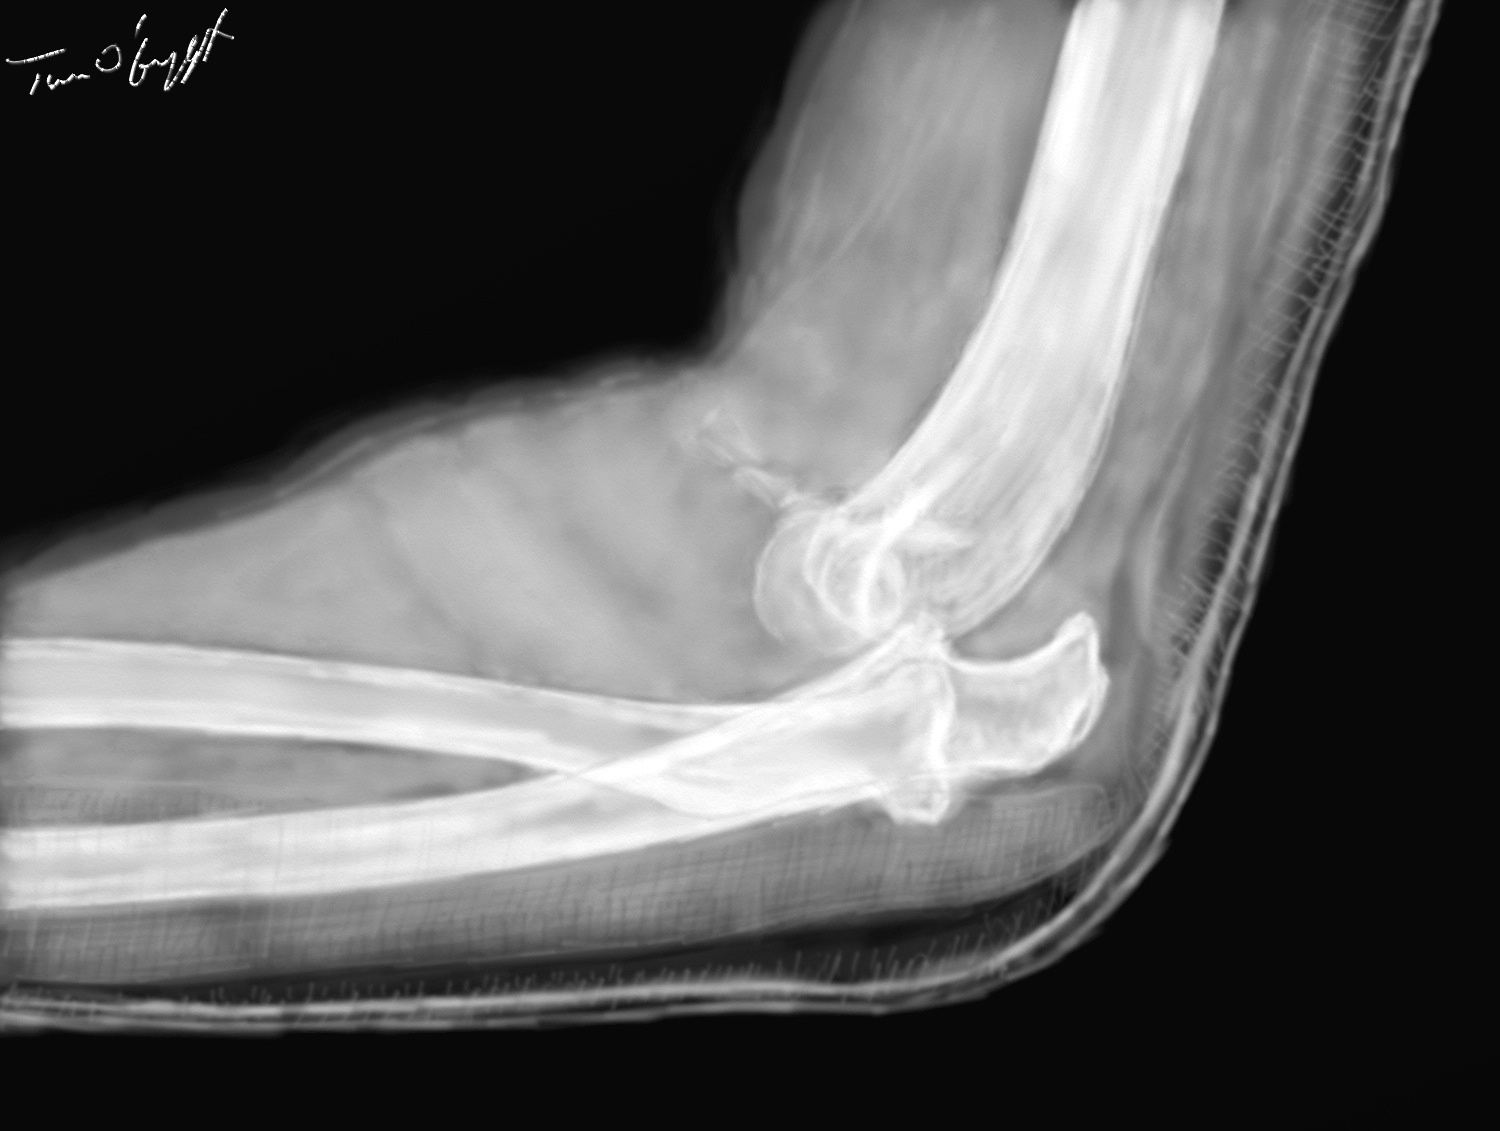

luxation postérieure du coude avec fracture du processus coronoïde du cubitus (radiographie de profil sous attelle plâtrée postérieure)

La luxation postérieure se produit en hyperextension. C’est l’ensemble épiphyses radiales et cubitales qui se déplacent vers le haut et l’arrière, tandis que la palette humérale passe devant le coude. Un stress ajouté en varus ou valgus entrainera un déplacement du cubitus soit médial/interne (côté cubitus) ou latéral/externe (côté radius). La luxation antérieure est causée par un coup porté sur l’arrière du coude avec l’articulation en légère flexion. La luxation isolée du cubitus est possible mais très rare. La luxation isolée de la tête radiale est un accident courant chez l’enfant, c’est la pronation douloureuse (nursemaid’s elbow). Chez l’adulte elle ne se voit pas, mais associée à une fracture du 1/3 supérieur du cubitus elle réalise la fracture de Monteggia.

La douleur est vive, parfois syncopale, la déformation du coude est importante et l’impotence fonctionnelle totale. Extérieurement on peut confondre avec une fracture importante du coude. A l’état normal un triangle équilatéral à sommet inférieur est formé par le sommet de l’olécrâne et les deux épicondyles de l’humerus sur un coude fléchi à 90°. Quand le coude est luxé ce triangle est soit dysharmonieux dans les luxations latérales soit devient isocèle avec proéminence de l’olécrâne dans les luxations postérieures. Le sommet disparait dans les luxations antérieures. A distance de la luxation une volumineuse ecchymose apparaitra dépassant largement la région du coude.

D’autres lésions ostéo-articulaires et des parties molles sont possibles. l’association luxation postérieure – fracture de la tête radiale – fracture du processus coronoïde du cubitus est désignée en anglais comme « terrible triad of the elbow ».